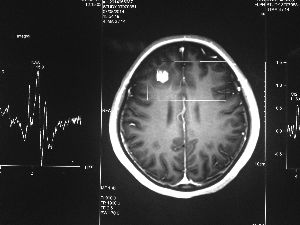

方框亮點(diǎn)為CT片顯示的異物

今年6月份,張敏在宿舍休息時(shí),又發(fā)起了癲癇,也是口吐白沫,渾身抽搐。送到蘇州一家大醫(yī)院,頭顱核磁共振檢查出,張敏大腦右額葉處有一處病灶,也就是大腦額頭處有個(gè)東西。

腦袋里的東西,到底是腫瘤還是其他什么東西,這個(gè)謎像個(gè)石頭一樣,壓得張敏一家人喘不過氣。7月份,張敏一家又來到南京腦科醫(yī)院求醫(yī),第三次檢查后,醫(yī)生覺得很像是寄生蟲。不過,影像的檢查,只能作為醫(yī)生推測(cè)的依據(jù),具體是什么,只有手術(shù)拿出來后才能知道。